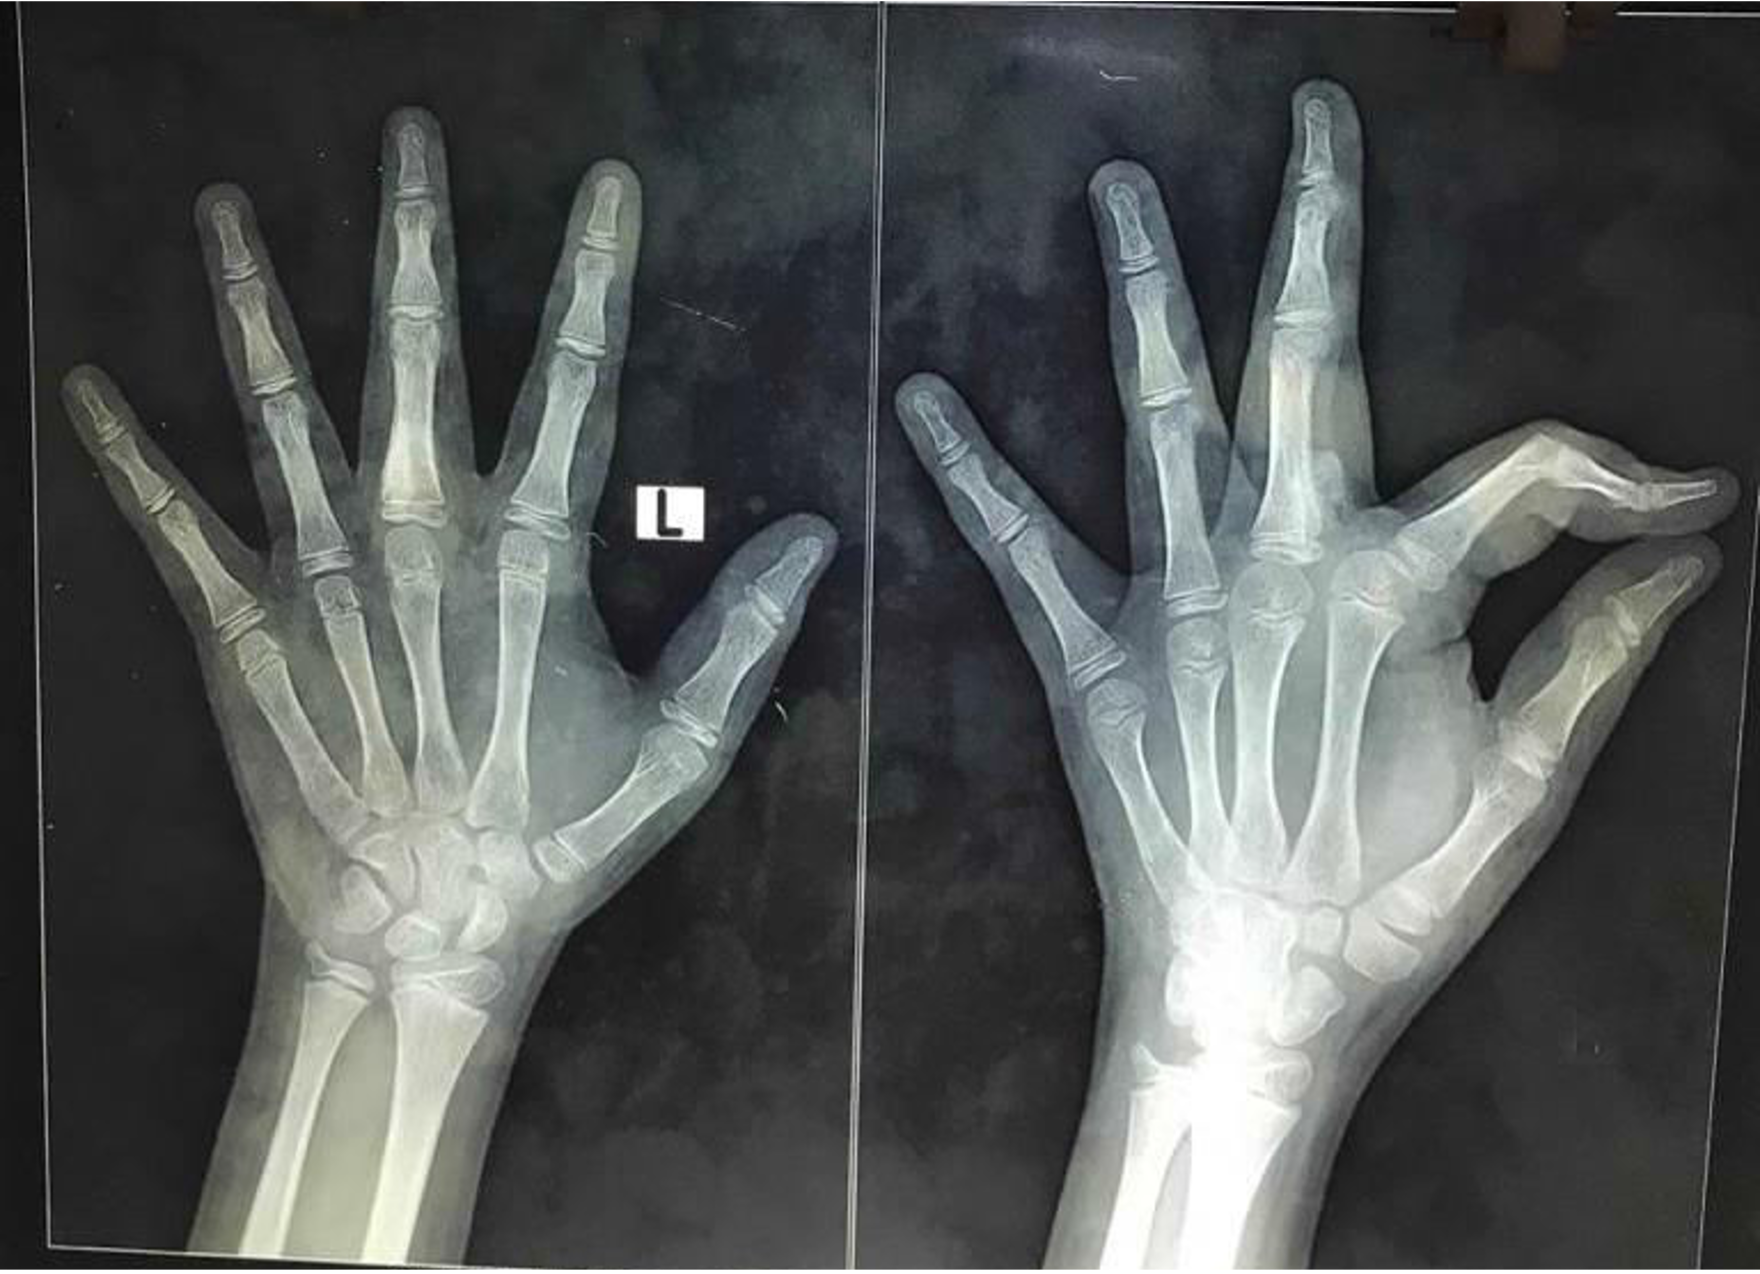

On examination, there was a well-defined single firm-to-hard non-tender swelling of about 2 x 1 cm in size on the volar aspect of his left middle finger extending from base to mid-shaft region of proximal phalanx (Figures 1,2,3). There was no associated angulation or shortening deformity. It was associated with minimal pain on deep palpation. There was restriction of flexion of the middle finger metacarpophalangeal joint (Figure 4; Video 1). Sensation was intact. He had no other swellings in his hands or rest of the body. X-ray showed a single irregular radiopaque lesion on the volar aspect of proximal phalanx of about 2 x 1 cm in size with no obvious angulation (Figure 5).

Ultrasound and computerized tomography (CT) of the hand were performed (Figure 6).

- CT of the hand report was a solitary pedunculated bony lesion with cortex and medulla of the lesion in continuity with proximal phalanx of middle finger. The lesion measures 1.8 x 0.7 cm, and base of lesion is 7.1 mm. Cartilage cap thickness is 2.2 mm. The rest of the phalanx of all fingers and metacarpals appear normal. Impression was osteochondroma of proximal phalanx of left middle finger.

Patient was started on early gentle active mobilization exercises within the dorsal pop under the supervision of trained hand therapist. Post-op x-ray showed complete tumor clearance (Figure 10). He was discharged on the 3rd postoperative day advising strict compliance to physiotherapy protocol.